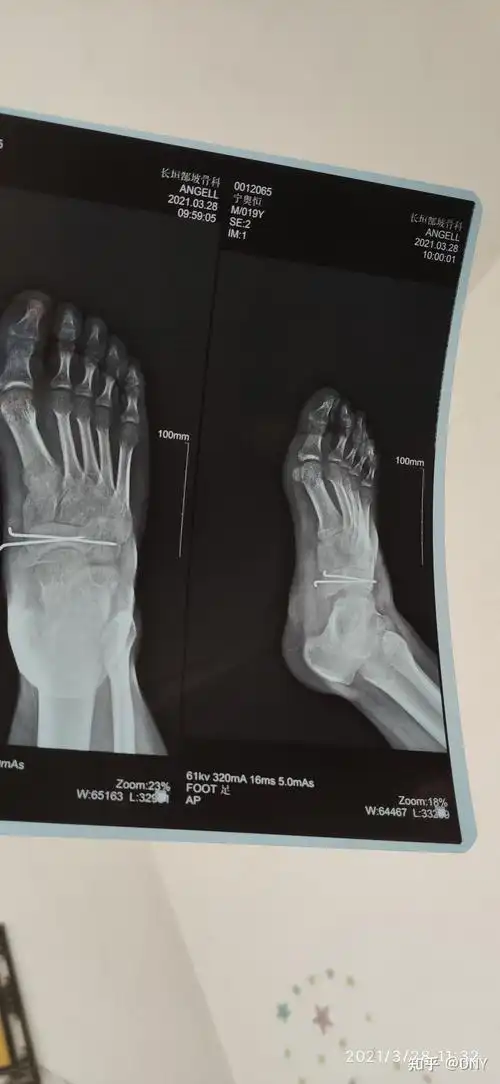

一例足舟骨第五跖骨基底粉碎性骨折的治疗

右足舟骨骨折恢复之路! - 知乎

骨科专业讨论版 关节 临床诊断:1,足舟骨骨折(骨骺?陈旧性骨折?